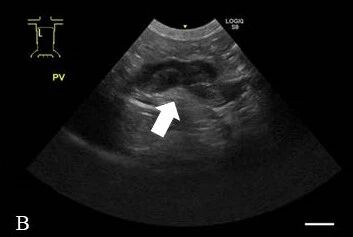

CT显示门静脉扩张和血栓(下图A)。

↑ 尸体CT成像和尸检的大体检查结果。(A)门静脉扩张和血栓(白色箭头)在CT多平面重建图像中可见。虚线表示门静脉。Liv:肝脏;St:胃;Kid:肾脏。(B)肝脏和胆囊:肝脏体积减小,肝脏表面不规则和变黄(黑色箭头),胆囊肿大伴胆汁淤积。(C)可见门静脉扩张和血栓(白色箭头)。(D)在左肾后侧附近可见多个分流(黑色三角),似乎是获得性的。

尸检和组织病理学检查结果包括梗阻性黄疸慢性肝炎和PVT(上图BC及下图)。